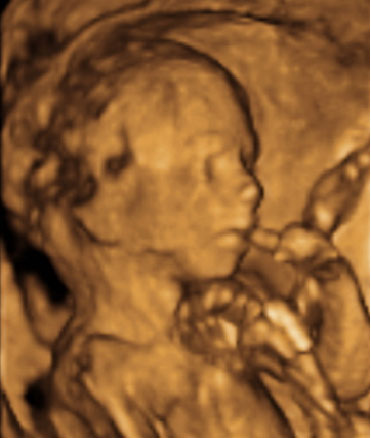

Con una edad gestacional de 20 semanas, este bebé está muy entretenido con un dedo en la boca. En esta ecografía de la semana 20, la morfológica, el especialista también mide el diámetro parietal del feto para comprobar su correcto desarrollo.

Cara y brazos de un feto de 20 semanas en ecografía 3D

Ecografía Embarazo 2D y 3D - SEMANA 20